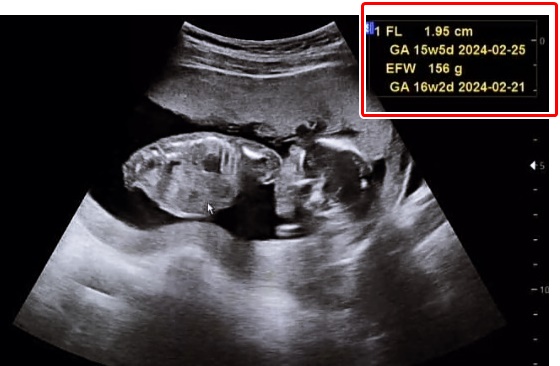

6. FL (Femur Length): 허벅지 길이

골반 밑부터 무릎뼈까지 사이(허벅지 다리길이), 넓적다리뼈 길이, 대퇴골의 길이입니다.

10. EFW (Estimated Fetal Weight): 태아 추정 체중

태아가 성장하면서 초음파로 태아의 모습을 전체적으로 보기 어려워지는데요.

이 때는 태아의 머리직경, 머리둘레, 복부둘레, 대퇴골 길이를 확인해 체중과 태아의 성장정도를 예상할 수 있습니다.

여러 신체 부위를 측정해 예상 키와 체중을 확인하게 됩니다.